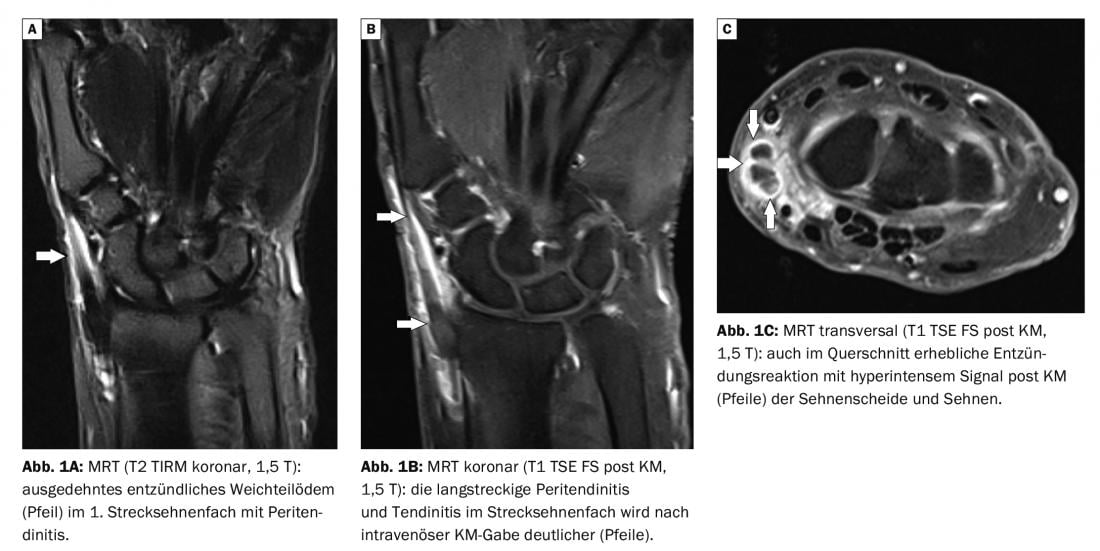

No estudo de caso 1 , uma paciente feminina de 64 anos foi suspeita de ter estenosans de Quervain (Fig. 1A a C) . Não houve nenhum trauma, queixou-se de um inchaço doloroso no pulso esquerdo radial e a extensão do polegar foi dolorosamente limitada. A ressonância magnética (RM) confirmou a suspeita; a inflamação no 1º compartimento do tendão extensor era clara, especialmente nas sequências de contraste. Uma ruptura do tendão ou alteração óssea significativa do pulso poderia ser excluída.

A ressonância magnética é o padrão dourado de imagem das alterações do ligamento inflamatório e dos tendões. Em particular, a aplicação intravenosa de agente de contraste mostra um claro aumento do sinal e a exacta extensão e actividade do evento inflamatório [1].